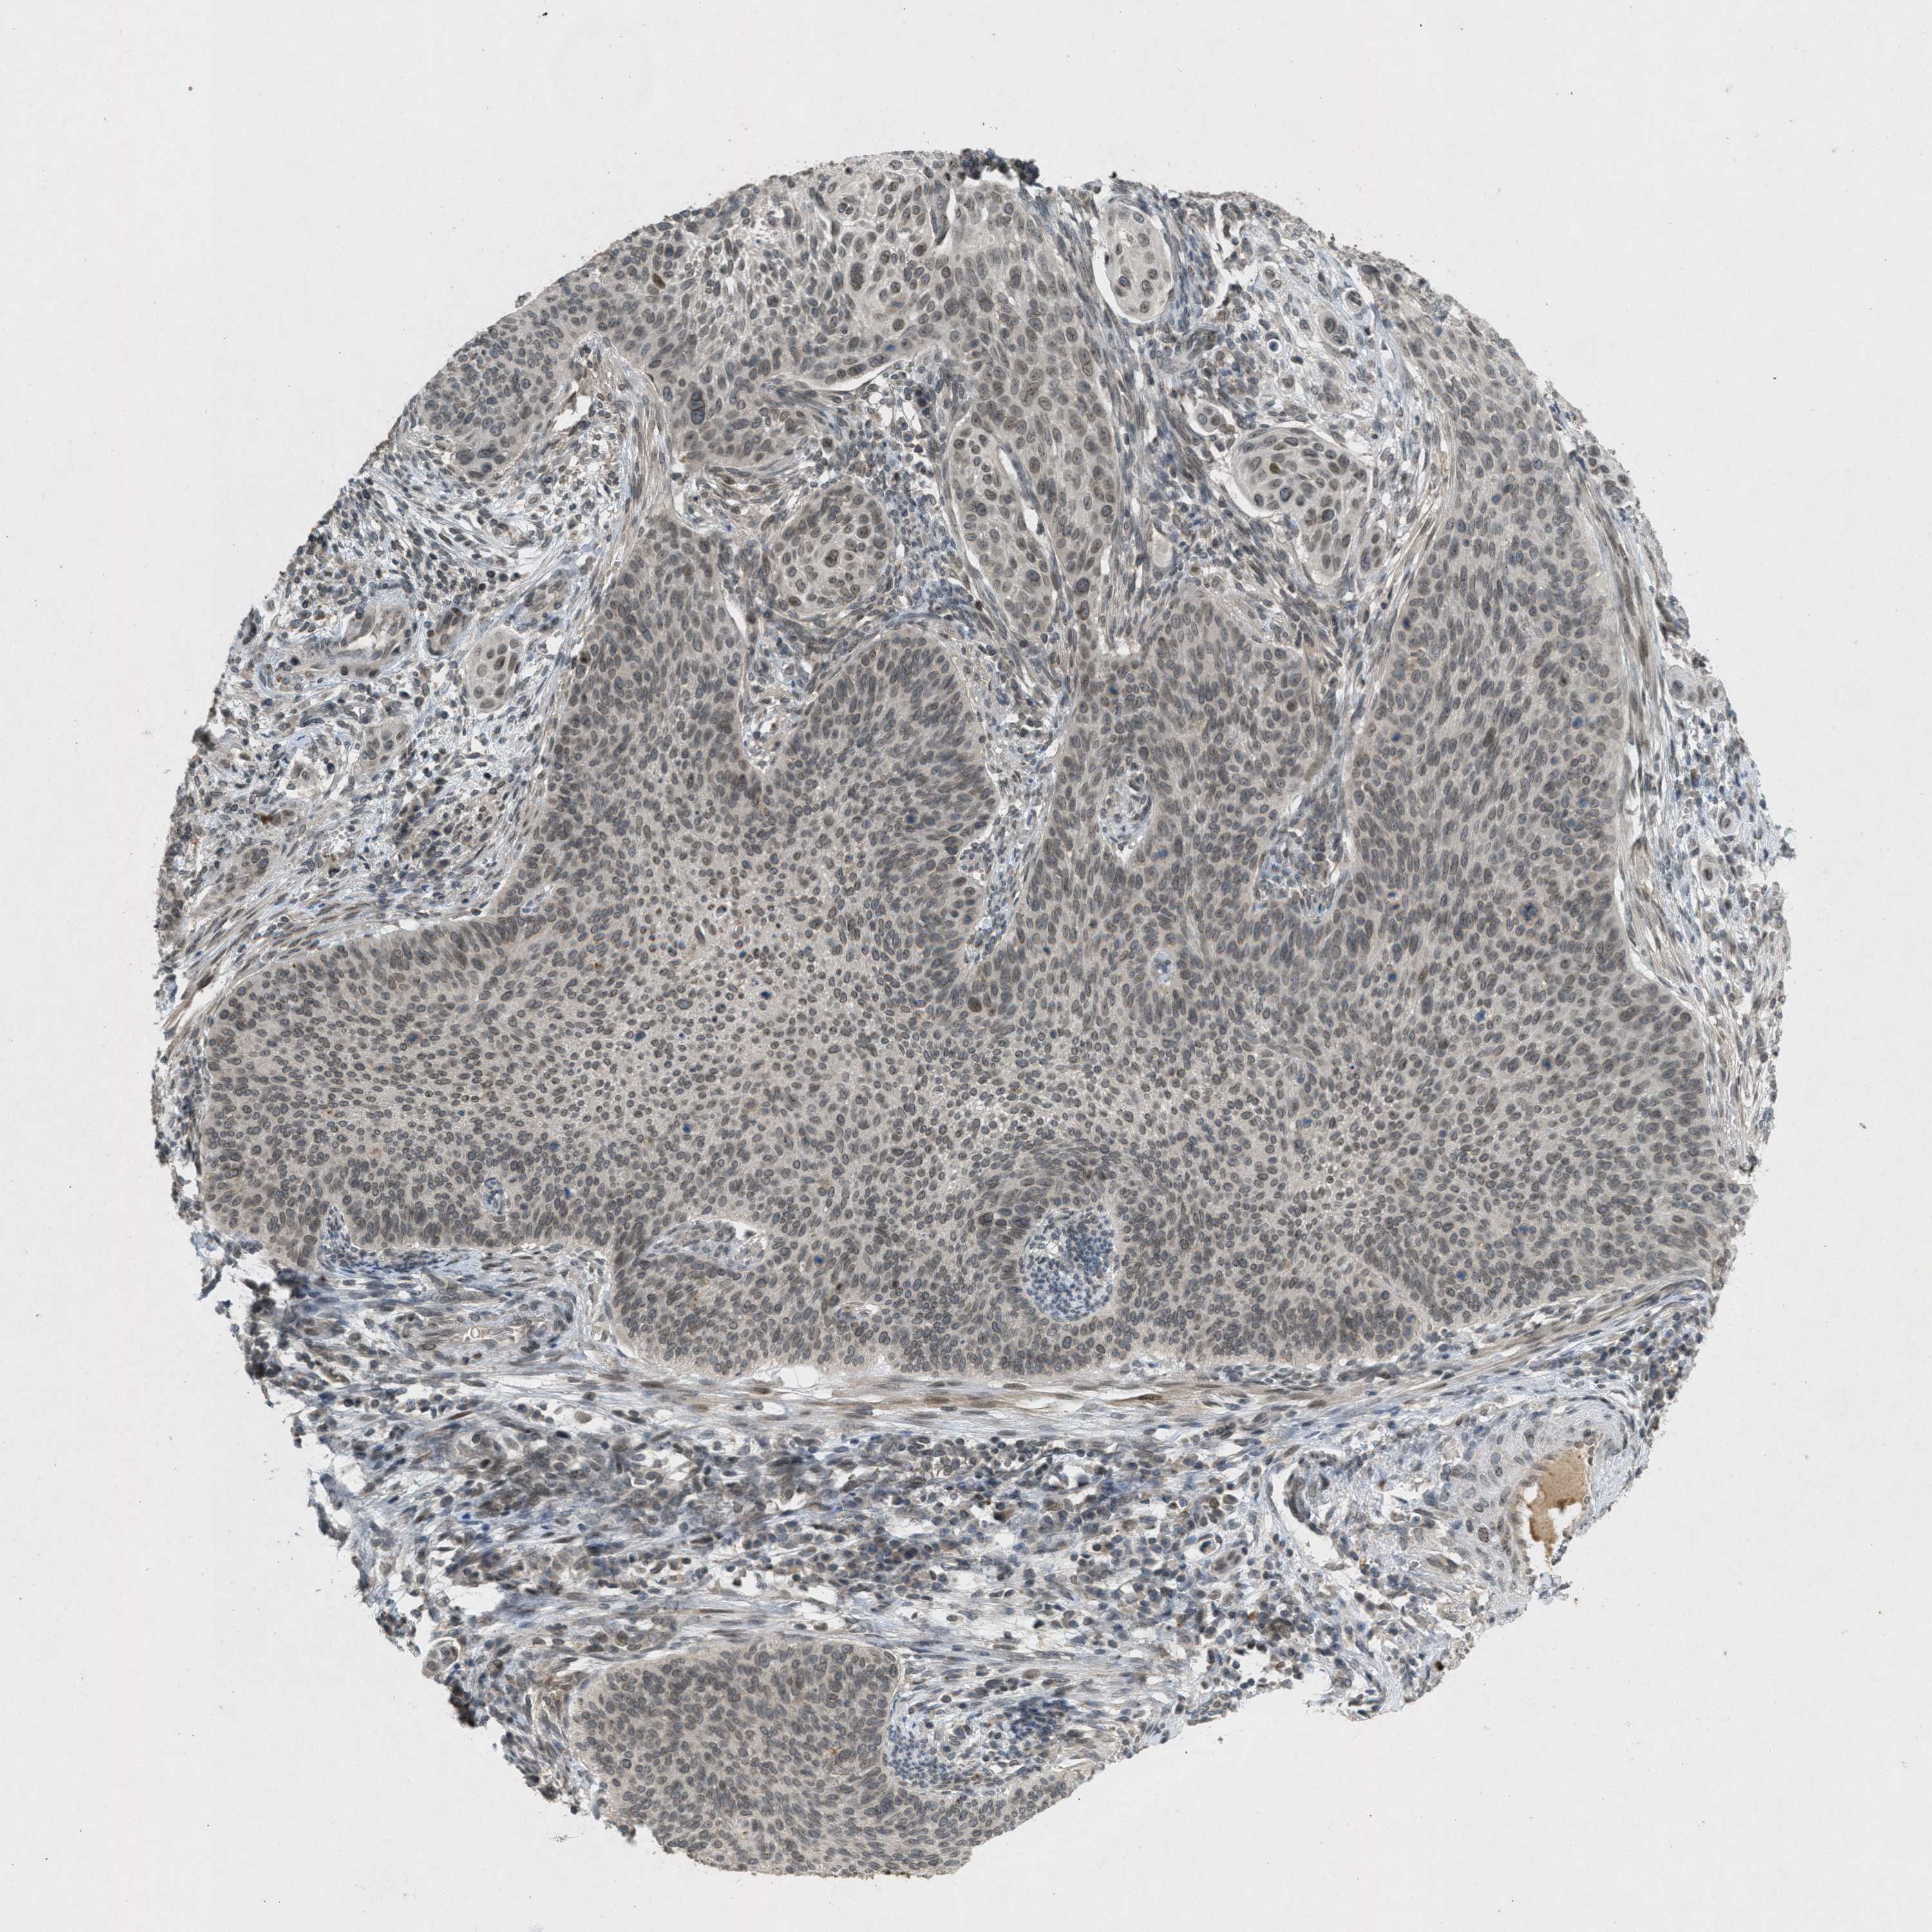

CERVICAL CANCER - Protein expressioni

A mouse-over function shows sample information and annotation data. Click on an image to view it in a full screen mode. Samples can be filtered based on level of antibody staining by selecting one or several of the following categories: high, medium, low and not detected. The assay and annotation is described here.

Note that samples used for immunohistochemistry by the Human Protein Atlas do not correspond to samples in the TCGA dataset.

Antibody stainingi

Antibody staining in the annotated cell types in the current human tissue is reported as not detected, low, medium, or high, based on conventional immunohistochemistry profiling in selected tissues. This score is based on the combination of the staining intensity and fraction of stained cells.

Each image is clickable and will lead to virtual microscopy that enables deeper exploration of all samples and also displays staining intensity scores, fraction scores and subcellular localization as well as patient and tissue information for each sample.

Antibody HPA017283

Staining

High

Medium

Low

Not detected

Intensity

Strong

Moderate

Weak

Negative

Quantity

>75%

75%-25%

<25%

None

Location

Nuclear

Cytoplasmic/membranous

Cytoplasmic/membranous,nuclear

Squamous cell carcinoma, NOS

Adenocarcinoma, NOS